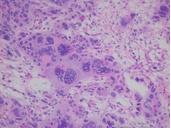

伤寒是伤寒杆菌引起的。主要的病理特征是全身网状内皮系统的增生反应,以回肠下段淋巴组织的病变最为显著。副伤寒,分别由副伤寒甲,乙,丙杆菌引起。它的临床表现、诊断、治疗和预防与伤寒相同。